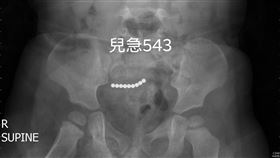

3歲童腹部見9個小白點 醫:破裂了

國內外發生多起孩童誤吞巴克球,造成腸道壞死的案例;一...

9歲童吞7顆巴克球 卡腸穿孔險致命

高雄一名9歲男童因為誤吞了七顆有強力磁性的巴克球,結...